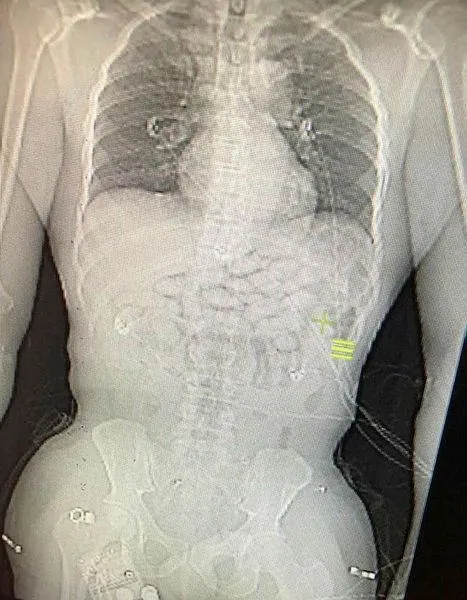

Yolcunun fenalaşması üzerine polis, yutma yoluyla uyuşturucu kuryeliği yaptığı şüphesiyle Ganalı yolcuyu gözaltına aldı. Hastanede yapılan kontrollerde şüphelinin röntgen ve tomografi görüntülerinde midesinde kapsüllerin içine gizlenmiş uyuşturucu madde tespit edildi.

Yapılan tıbbi müdahalenin ardından Ganalı yolcunun yuttuğu içinde metamfetamin olan 93 adet kapsül midesinden çıkartıldı.